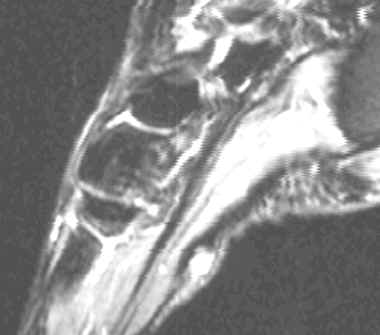

Characterized by nodular or poorly defined aggregates of mature to somewhat immature fibroblasts dispersed throughout dense collagen, causing irregular or nodular subcutaneous thickening of the plantar fascia. On MR, this appears as a nodular thickening of the plantar aponeurosis, which has low to intermediate signal intensity on both T1 and T2W images. Central increased signal intensity may be present.

62-year-old male with nodular thickening of the plantar fascia. This has intermediate signal on T1W and hyperintense signal on T2, proton density and Stir weighted images. These are atypical signal characteristics of plantar fibromatosis.